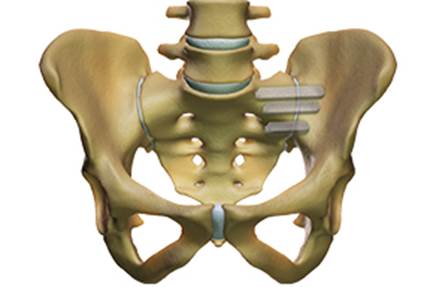

Surgical treatment of the painful SI joint is indicated only in cases where conservative therapy has failed for longer than 6 months. If the chronic SI joint pain persists, minimally invasive surgery can be performed: it consists of the percutaneous placement of three triangular titanium implants that block the ilium and sacrum bones, blocking the SI joint in all its degrees of freedom.

Characterization of percutaneous surgical fusion of the left sacro-iliac

joint by means of 3 titanium implants with triangular profile.

In recent years, more than 30,000 procedures have been performed worldwide. Clinical studies show a significant improvement in a patient’s quality of life after surgery compared to patients treated without surgery.

Dr. Morgenstern is an accredited surgeon for the percutaneous fusion of the sacroiliac joints.